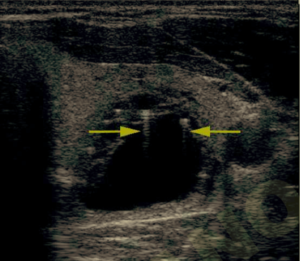

Salve, Ho effettuato un ecografia addome completo, per familiaririta di primo grado (mia madre) per neoplasie della colecisti e pancreas

ll referto riporta nulla da segnalare, tranne

La colecisti che e’

Normoconformata con pareti regolari a parte 2 riverberi a stria di cometa di parete ecopriva